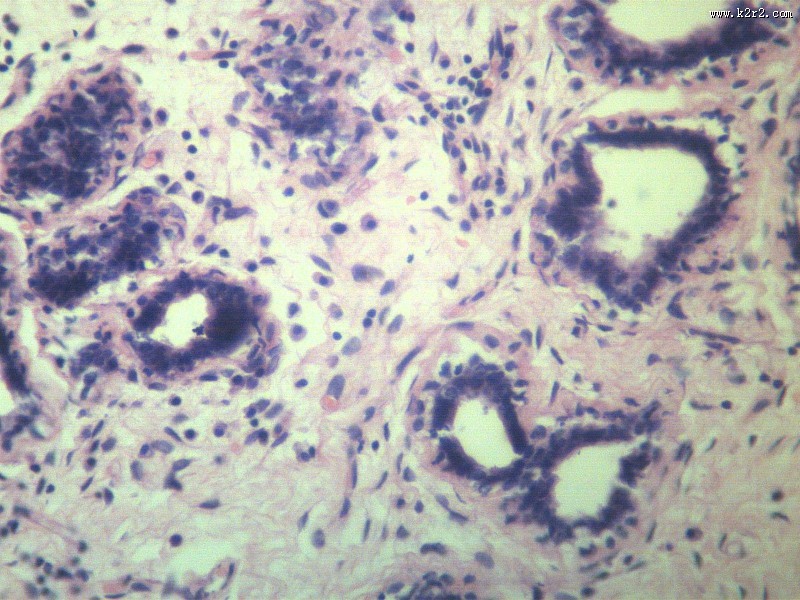

乳腺纤维腺瘤 - 第10张

乳腺纤维腺瘤

fibroadenoma of breast

肿瘤显微切片